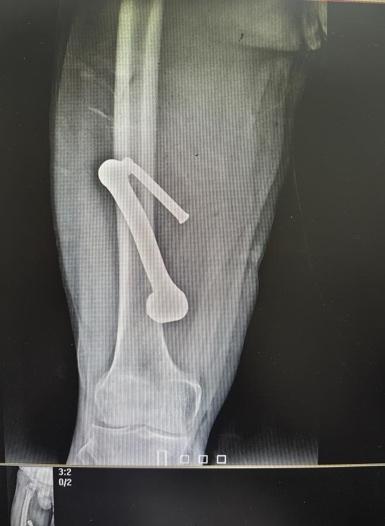

张先生被紧急送至该院急诊室。三维血管造影检查显示,金属异物位置极为凶险:其穿行路径紧邻人体主要动脉之一的股动脉。异物与股动脉间距极小,一旦损伤该血管,将导致快速致命性大出血,需紧急处置。

徐楚江带领团队进行了精细的手术操作。术中发现金属异物与股动脉、股静脉紧密粘连,距离坐骨神经仅几毫米距离。手术需要极高的操作精度,稍有不慎就可能损伤重要血管或神经,引发大出血或永久性神经功能损伤,严重时会导致下肢瘫痪。经过一个多小时的谨慎操作,医护团队成功将异物与周围血管、神经分离,完整取出金属异物。